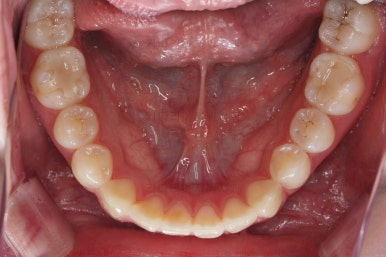

각설하고 위의 사진들은 부산치아교정잘하는곳 키다리아저씨치과에서 처음 내원하셨을 때의 사진입니다.

아랫니는 크게 심하지 않았고 윗니 앞니쪽에 치열이 삐뚤한 것을 볼 수 있어요.

그리고 위아랫니의 중앙선도 어긋나 있는 것으로 봐서 왼쪽과 오른쪽의 교합 자체도 다르고 문제가 있음을 알 수 있었어요.

가장 좋은 교합은 위아래 치아들이 지그재그로 톱니바퀴 물리듯이 맞아들어가야 하는데 오른쪽 사진들 보면 중간중간 빈틈도 많이 보여요.

이런 교합은 장기적으로 치아 수명을 단축시킬 수 있습니다.